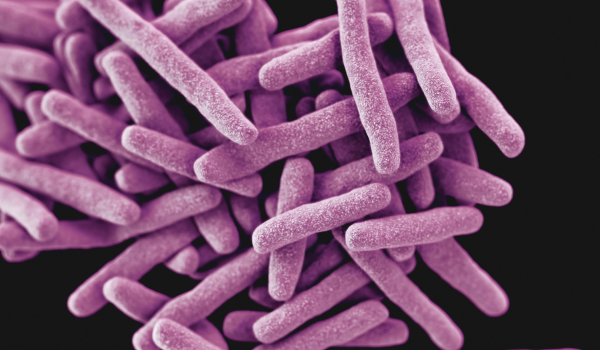

Mycobacterium - tål många biocider

Vanligt förekommande i skärvätskor är mykobakterier, däribland M. chelonae, M. immunogenum och M. avium. Mykobakterier är opportunistiska patogener och tros vara orsaken till allergisk alveolit ("Hypersensitivity pneumonitis") hos människor som exponerats för skärvätskeaerosoler. Allergisk alveolit har symptom såsom feber, andfåddhet, torrhosta samt muskel- och ledbesvär som uppstår inom ett par timmar från exponering och varar i ungefär ett dygn. Vid upprepad exponering kan kroniska besvär uppstå. En anledning till att mykobakterier är så vanliga är att de är resistenta mot flertalet biocider. När övriga bakterier i en skärvätska slås ut av biocider får därför mykobakterierna en unik chans att bli den dominerande floran.